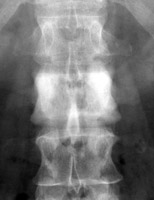

A uniformly white vertebra with no abnormality of its contour or adjacent disks. The vertebra stands out against the adjacent normal, or darker, vertebral bodies. While the list of possible etiologies of ivory vertebrae is extensive, the most common causes of ivory vertebrae are typically metastatic disease, and Paget’s. A-B. Metastatic breast cancer. C-D. Paget's disease.

Lateral lumbar spine - Click on the image for a larger versionAAP lumbar spine - Click on the image for a larger versionBIvory Vertebra - Click on the image for a larger versionCIvory Vertebra - Click on the image for a larger versionD